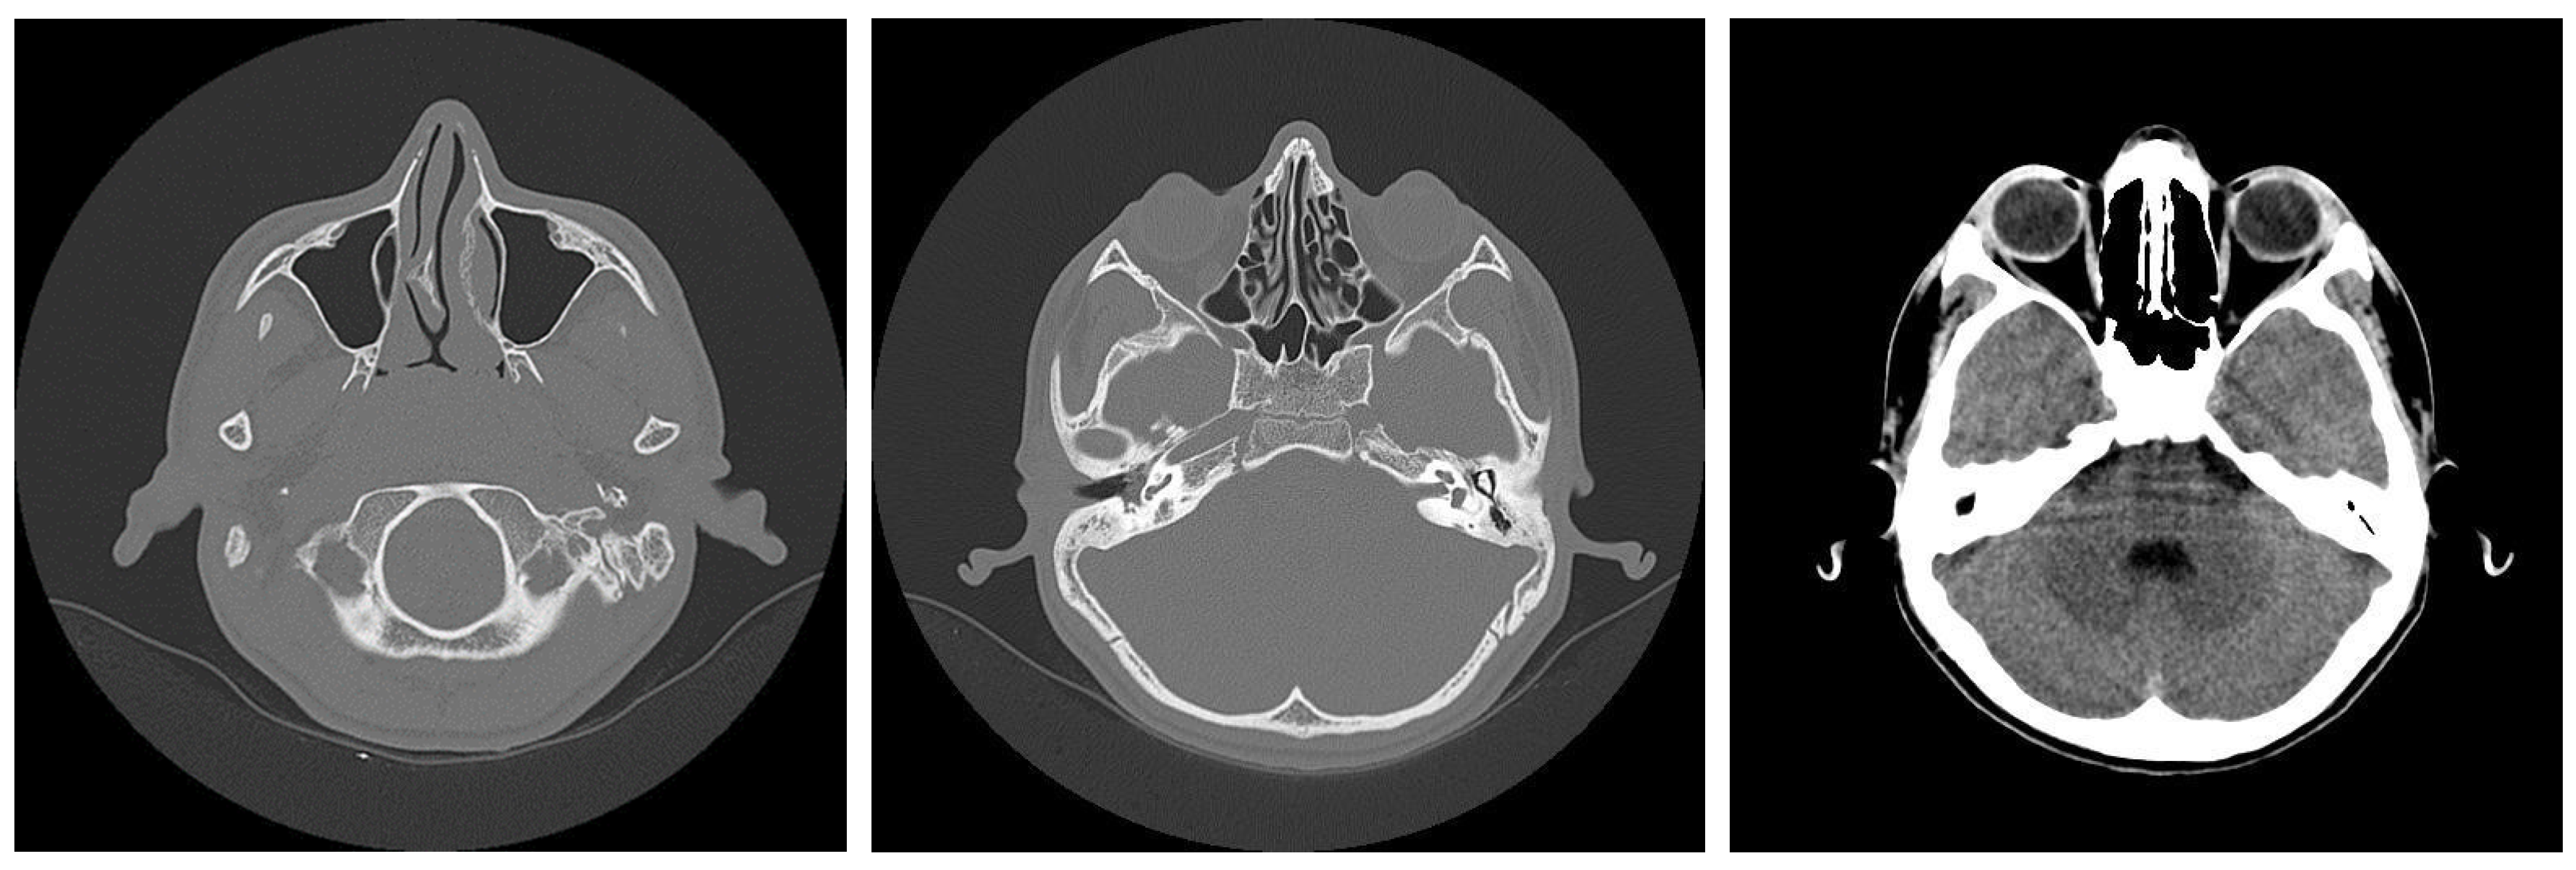

3.1.2. Computed Tomography and Magnetic Resonance Imaging

| CT Aspects | Number of Patients | Percentage |

|---|---|---|

| Fluid accumulation | 168 | 100% |

| Osteolysis | 152 | 90.47% |

| Osteocondensations | 128 | 76.19% |

| Cholesteatoma | 48 | 28.57% |

| Exocranial extensions | 48 | 28.57% |

| Intracranial extensions | 24 | 14.28% |

| Changes to the external auditory canal | 68 | 40.47% |

| Ossicular chain damage | 144 | 85.71% |